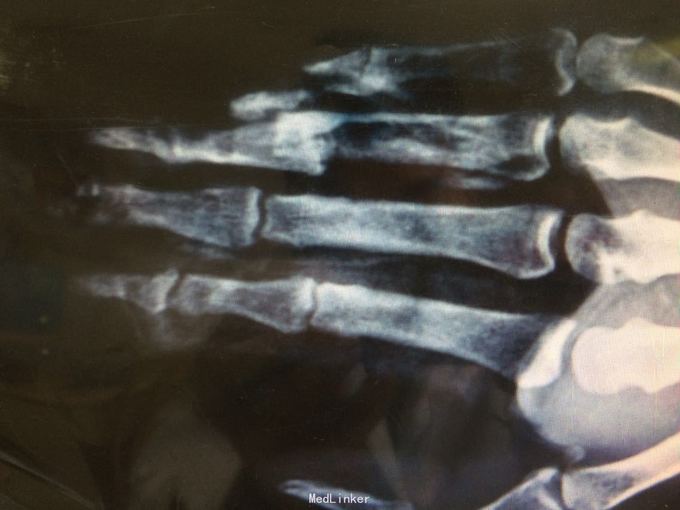

手外伤

手外伤术前于术后